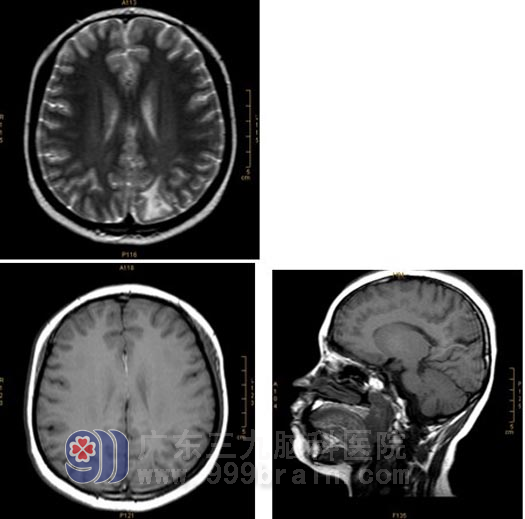

X-刀治疗半年后:原左顶叶病灶内流空信号异常血管已消失;左顶叶畸形血管团较前明显缩小,左大脑中动脉远端较前稍变细。